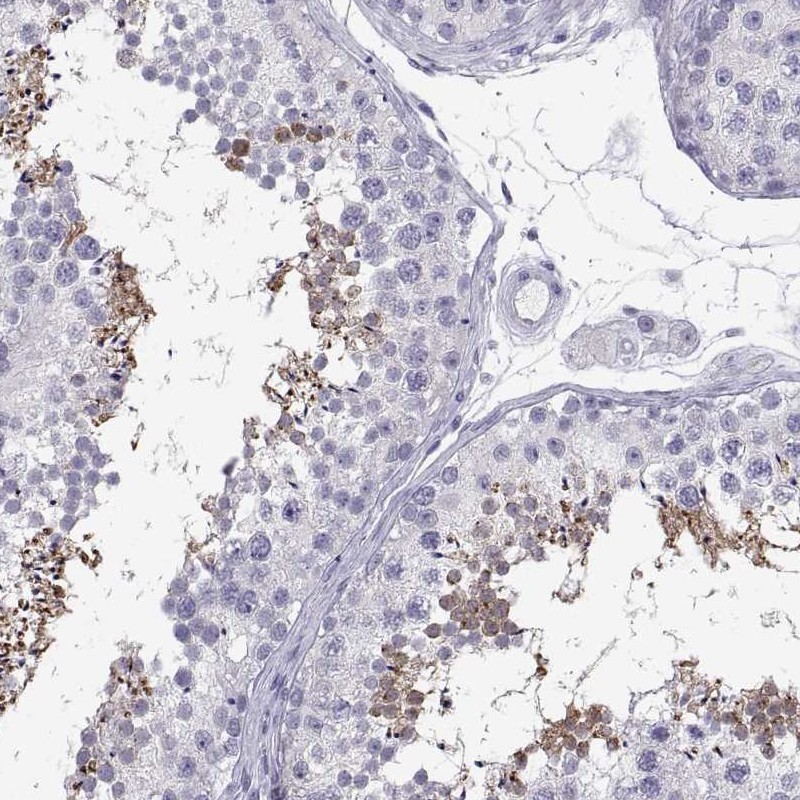

Immunohistochemistry analysis in human testis and endometrium tissues using Anti-TEX13A antibody. Corresponding TEX13A RNA-seq data are presented for the same tissues.